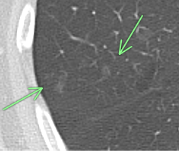

矢印の部位に8㎜大の結節(充実型)を認めました。

6年の経過で8㎜から11㎜大に増大したため、手術が行われましたが、早期肺がんでした。

胸部CTで○枠、矢印の部位に8㎜大の結節(充実型)を認めました。